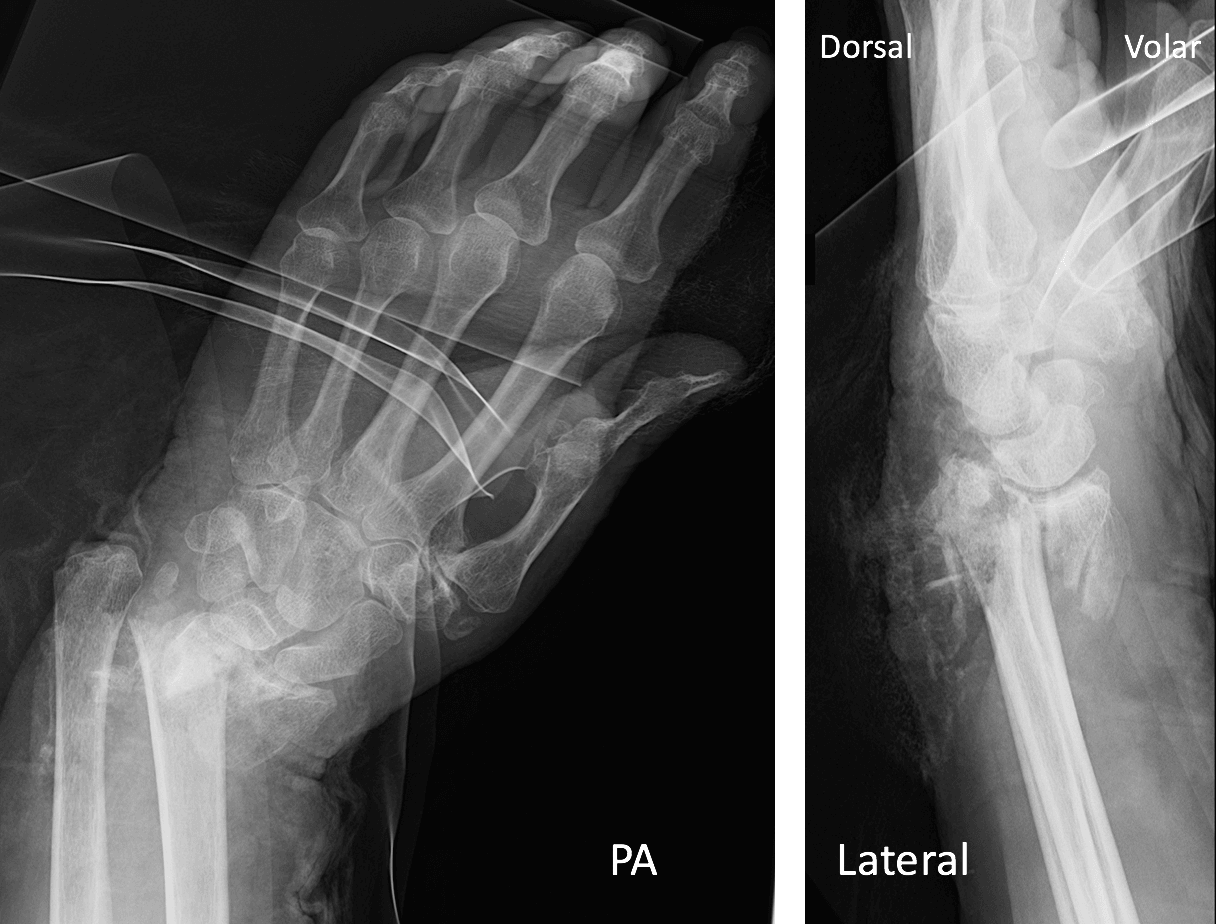

Distal End Radius Reduction . Distal radius fracture is one of the most common orthopedic injuries, and indications for closed management techniques should be understood. With the advent of the volar locking plate, open reduction and internal fixation techniques have increased in popularity due to more stable fixation allowing earlier range of motion. Fracture of the distal radius is a common clinical problem. Displaced fractures are usually reduced using closed reduction methods,. The goals of treatment of distal radius fractures include restoration of length, reduction of articular step off, restoration of palmar tilt, restoration of. Distal radius fractures are the most common orthopaedic injury and generally result from fall on an outstretched hand. Distal radius, open reduction and internal fixation using volar locked plates have gained popularity in recent times and has shown promising results in.

The goals of treatment of distal radius fractures include restoration of length, reduction of articular step off, restoration of palmar tilt, restoration of. Distal radius fractures are the most common orthopaedic injury and generally result from fall on an outstretched hand. Distal radius fracture is one of the most common orthopedic injuries, and indications for closed management techniques should be understood. With the advent of the volar locking plate, open reduction and internal fixation techniques have increased in popularity due to more stable fixation allowing earlier range of motion. Fracture of the distal radius is a common clinical problem. Displaced fractures are usually reduced using closed reduction methods,. Distal radius, open reduction and internal fixation using volar locked plates have gained popularity in recent times and has shown promising results in.

Distal End Radius Reduction Displaced fractures are usually reduced using closed reduction methods,. Distal radius fractures are the most common orthopaedic injury and generally result from fall on an outstretched hand. The goals of treatment of distal radius fractures include restoration of length, reduction of articular step off, restoration of palmar tilt, restoration of. Distal radius, open reduction and internal fixation using volar locked plates have gained popularity in recent times and has shown promising results in. With the advent of the volar locking plate, open reduction and internal fixation techniques have increased in popularity due to more stable fixation allowing earlier range of motion. Distal radius fracture is one of the most common orthopedic injuries, and indications for closed management techniques should be understood. Displaced fractures are usually reduced using closed reduction methods,. Fracture of the distal radius is a common clinical problem.